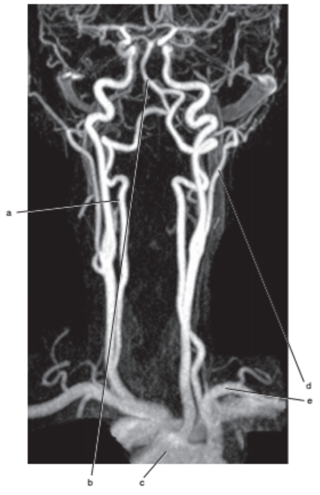

What is letter a ?

Vertebral artery